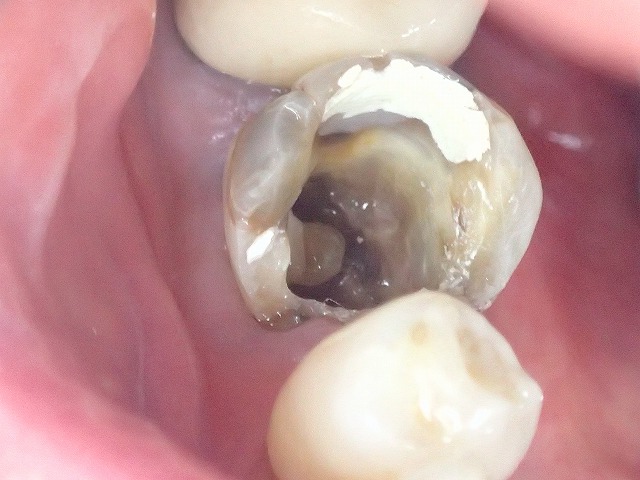

別の症例の象牙真珠

真ん中に丸い二次象牙質

これが象牙真です。

歯が全体的にグレーなのは

テトラサイクリン着色と呼ばれる

元々からの着色ですが

遠心部分から虫歯が見られます。